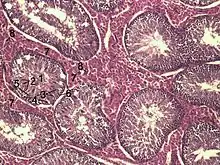

En coupe histologique des testicules après coloration PAS (periodic acid Schiff), les spermatogonies Ad (le d désignant dark) sont noirs et les spermatogonies Ap (p désignant pâle) sont claires.